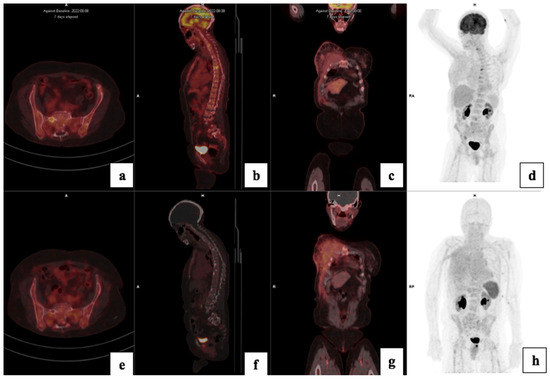

3.5. Treatment Response